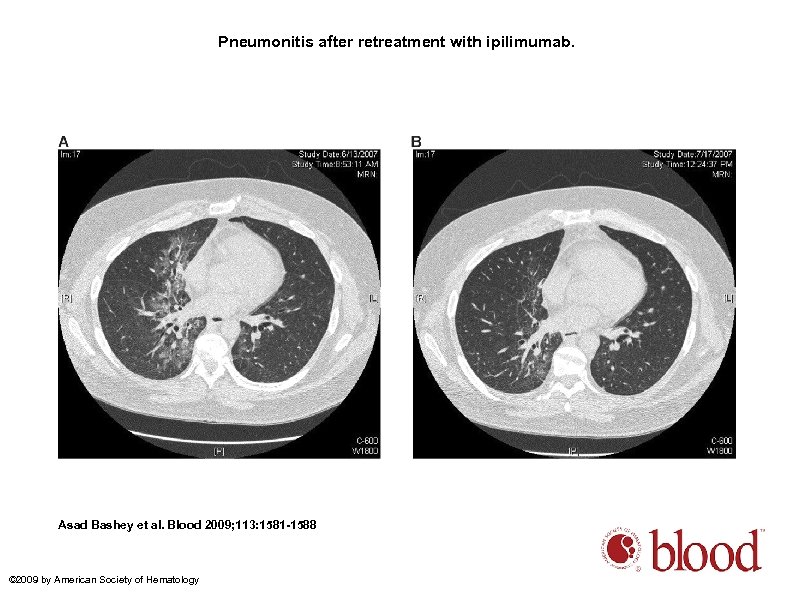

Pneumonitis after retreatment with ipilimumab. Asad Bashey et al. Blood 2009; 113: 1581 -1588 © 2009 by American Society of Hematology